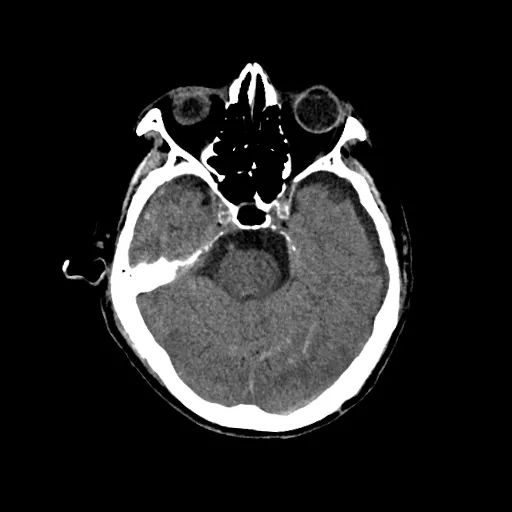

病例(二)

患者病史:86岁男性,脑损伤入院,治疗后复查

CT检查:行头部平扫,扫描条件:120 kv,280 mAs,重建层厚4.5 mm

CT图像:窗位/窗宽:38/80

图3

蛛网膜下腔出血,

硬膜下腔积液

影像描述:颞顶叶可见斑片高密度影,两侧额颞顶部颅板下见弧形低密度影

影像诊断:颞顶叶血肿,两侧额颞顶部硬膜下积液

病例结果:蛛网膜下腔出血